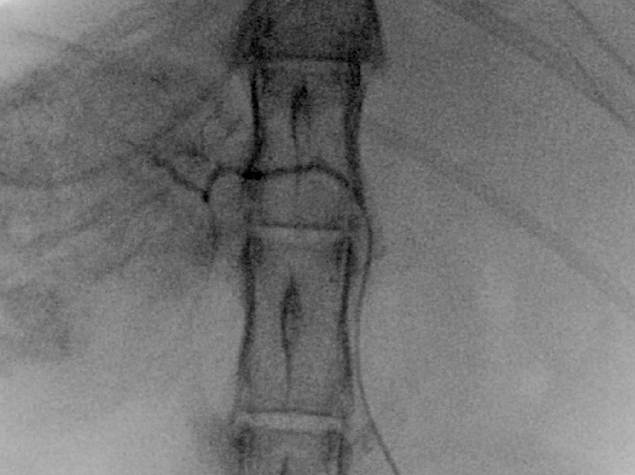

TAE

腹腔動脈選択~腹腔動脈造影

4Fr RADIFOCUS INTRODUCER(TERUMO)

4.2Fr RIM-S型 catheter(Hanako Medical)

総肝動脈選択~feeder選択

1.7Fr Estream micro catheter(東レ)

0.014inch Cross Winder(東レ)

塞栓剤注入

ジェルパート1mm 粒(日本化薬)